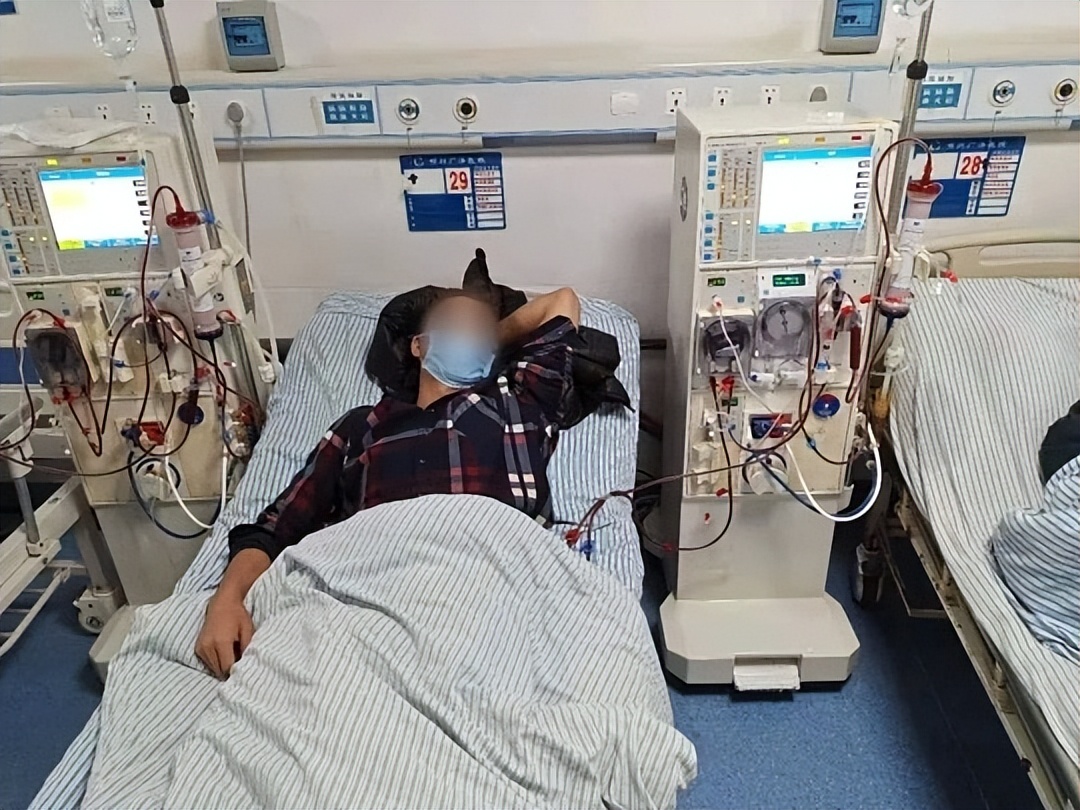

43歲的王先生,一天跑廁所8次,夜裡還要起來兩次,開始他以為是「前列腺」,後來檢查一做,醫生眉頭一皺:腎小球濾過率只剩下原來的三分之一,已經是中度腎功能不全的邊緣狀態。這不是個例。現在的很多「亞健康」,其實都是「慢性病前夜」的隱形信號。尤其是腎臟,它不像骨頭一斷就疼,不像胃一發炎就嘔。它慢,它沉,它默不作聲地被你一點點耗盡。腎衰竭不是老年病,它是「生活方式病」。

你早上空腹咖啡,中午外賣重口味,晚上聚餐擼串啤酒,睡前刷手機熬夜到一點……這些看似無害的生活小事,堆起來就是腎的「慢性謀殺」。在臨床上,有個詞叫「慢性腎病的五期旅程」,從最初的輕微蛋白尿,到最後的透析依賴,很多人都是一步步走到這一步。不是突如其來,而是日積月累。